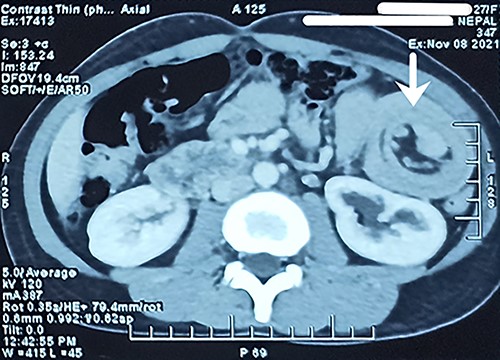

Biochemical and hematological investigations were unremarkable with a total leukocyte count of 8.9 K/μl and a hematocrit of 39.3%. Liver function tests, pancreatic enzymes and electrolytes were within normal range. Plain computed tomography (CT) scan (Fig. 1) of the abdomen revealed ~9.6-cm length long segment invagination of proximal jejunal loop into lumen of immediate distal jejunum. Another similar ~7.7-cm long segment invagination of ileum into lumen of immediate distal ileum was seen. No definitive features of bowel obstruction were seen. There were few enlarged mesenteric lymph nodes seen at the neck of the lesion measuring up to 16 × 11 mm.

Long segment invagination of proximal jejunal loop into lumen of immediate distal jejunum.